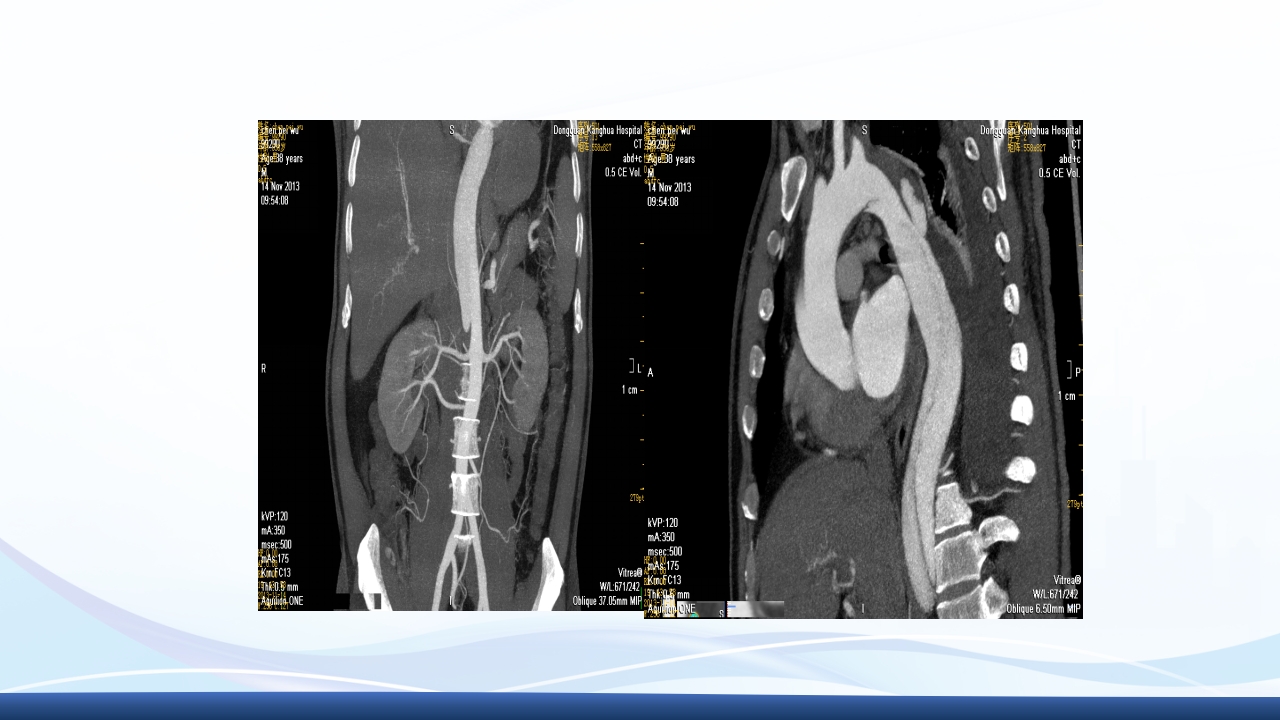

大纲 1 主动脉夹层的概念 2 病因与发病机制、分型 3 临床表现3 、辅助检查 4 主动脉夹层的诊断、治疗 5 病例介绍 64 护理诊断与措施、健康宣教 解剖图 解剖图 主动脉夹层的概述 主动脉夹层(aortic dissection AD)指主动脉壁中层 撕裂、分离,使主动脉壁内形成血肿,并沿纵向延伸。 AD最常发生在50-70岁的男性,男女性别比约2-5:1, 是与人类主动脉有关的最常见的死亡原因。 Thoraci caorta Abdomin alaorta Aortic dissection Aorta Blood in wall of artery Blood in artery 病因 结缔组织遗传缺陷性疾病:如马方(Marfan)综合征、埃-当(Ehlers-Danlos)综 合征、先天性主动脉缩窄、二叶主动脉瓣及二尖瓣脱垂等患者。 高血压:临床与动物实验发现,不是血压的高度...